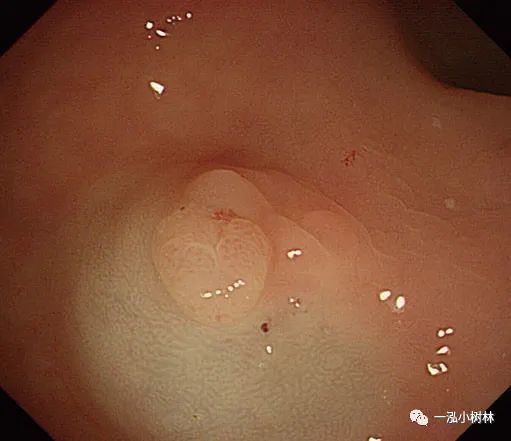

图2a 横结肠3mm大小0-IIa型息肉

图2b 病灶活检钳咬除

图2c 病变是完全被活检钳所钳除

图2d 在同一部位未发现肿瘤残留